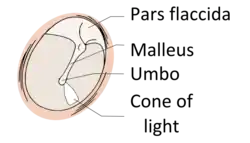

The eardrum is divided into two general regions: the pars flaccida and the pars tensa.[3] The relatively fragile pars flaccida lies above the lateral process of the malleus between the Notch of Rivinus and the anterior and posterior malleal folds. Consisting of two layers and appearing slightly pinkish in hue, it is associated with Eustachian tube dysfunction and cholesteatomas.[4]

The larger pars tensa consists of three layers: skin, fibrous tissue, and mucosa. Its thick periphery forms a fibrocartilaginous ring called the annulus tympanicus or Gerlach's ligament.[5] while the central umbo tents inward at the level of the tip of malleus. The middle fibrous layer, containing radial, circular, and parabolic fibers, encloses the handle of malleus. Though comparatively robust, the pars tensa is the region more commonly associated with perforations.[6]

Umbo

The manubrium (Latin: handle) of the malleus is firmly attached to the medial surface of the membrane as far as its center, drawing it toward the tympanic cavity. The lateral surface of the membrane is thus concave. The most depressed aspect of this concavity is termed the umbo (Latin: shield boss).[7]

When the eardrum is illuminated during a medical examination, a cone of light radiates from the tip of the malleus to the periphery in the anteroinferior quadrant, this is what is known clinically as 5 o'clock.